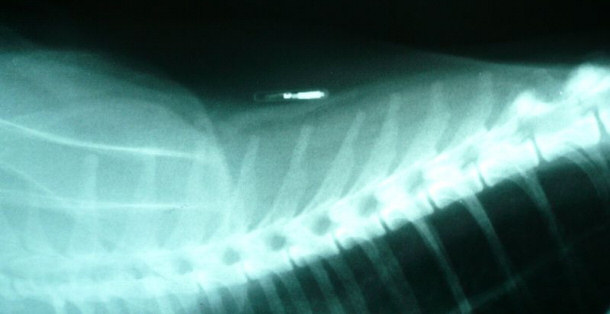

Qu’est-ce qu’une micropuce? Il s’agit d’un petit dispositif de la grosseur d’un grain de riz sauvage qui sera injecté sous la peau de votre animal, généralement au niveau des omoplates. Cette minuscule puce informatique est dans une capsule de matériel lisse inerte, qui ne causera aucune réaction à l’organisme de votre animal. Cette micropuce comprend un numéro à 15 chiffres unique. Quand vous faites micropucer votre animal, vous enregistrez ce numéro dans une immense banque de données qui reliera votre animal à vous. La lecture de la micropuce se fait facilement à l’aide d’un lecteur universel approprié. La majorité des refuges et des vétérinaires possèdent ce lecteur et scannent de routine les animaux trouvés. Il faut faire attention toutefois; il ne s’agit que d’un dispositif d’identification! Il ne s’agit en aucun cas d’un GPS qui permettra d’indiquer la localisation de votre animal.

La micropuce en tant que telle est indolore. Son installation quant à elle ne demande qu’une simple injection, donc votre animal ressentira un pincement au moment de l’entrée de l’aiguille sous la peau, sans plus. Beaucoup de propriétaires de jeunes animaux vont faire installer la micropuce pendant que l’animal est sous anesthésie lors de la stérilisation pour lui éviter de sentir la piqure. Mais cette procédure peut être faite sans problème chez un animal réveillé. L’installation d’une micropuce n’est pas dispendieuse et varie selon les cliniques vétérinaires de 30 à 60$. Il vous faudra ensuite débourser un petit montant pour enregistrer votre animal dans une banque de données. Attention, certaines chargent des frais annuels ou ne permettent pas le transfert de l’animal.